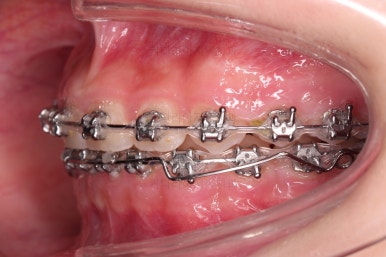

초진 시 입안의 모습입니다.

앞니가 안으로 굽어 들어간 양상인데요. 흔히 "옥니"라고 표현합니다.(뻐드렁니의 반대개념)

전반적으로 치열이 삐뚤삐뚤하고요.

오른쪽 상단 사진을 보시면 어금니의 높이와 앞니의 높이가 차이가 많이 납니다.

앞니가 솟구쳐 있는 양상인데요.

그 이유 때문에 어금니로 다물었을 때의 위아래 앞니가 많이 겹쳐서 아래 앞니가 아예 보이지 않는 상황이었어요.

이를 "과개교합"이라고 표현합니다.

그리고 전반적으로 아래 치열이 윗니에 비해 뒤로 밀려 있어서, 어금니의 맞물림이 좋지 못하고 듬성듬성해 보이는 상황이었어요.